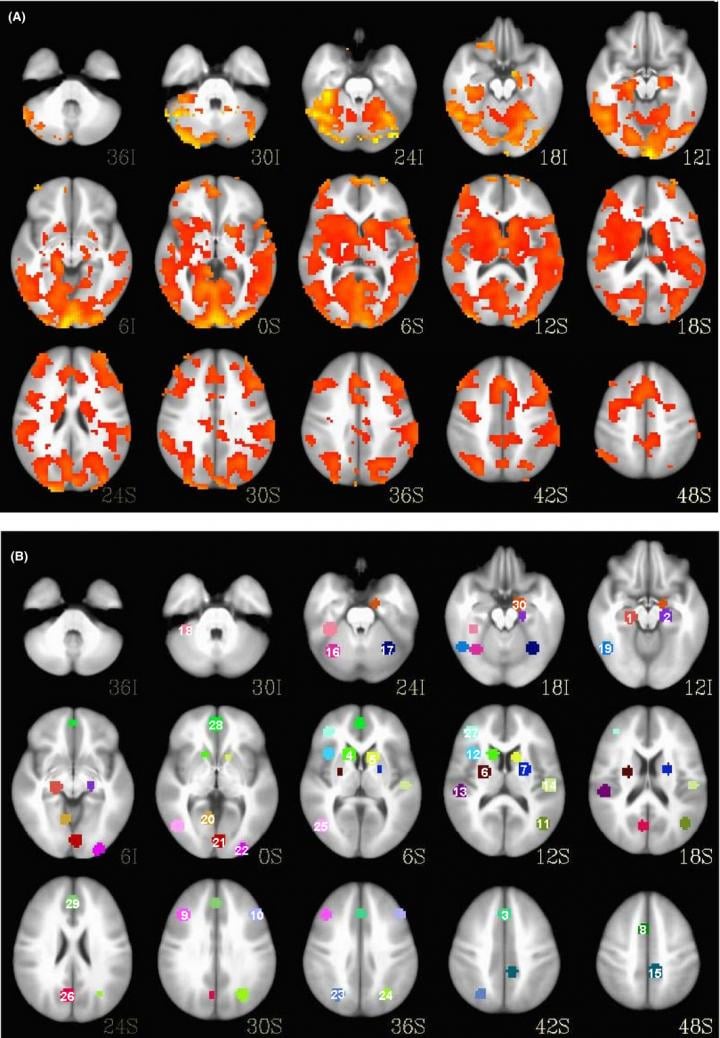

(PDF) Using structural MRI to identify bipolar disorders 13 site Does Bipolar Show Up On Mri Despite decades of research, the pathophysiology of bipolar disorder (bd) is still not well understood. these studies have demonstrated that patients with bipolar disorder show trait brain functional activations in the limbic system (eg,. however, as research advances, more evidence may help doctors use mri scans or other imaging technology to accurately diagnose bipolar disorder. mris and. Does Bipolar Show Up On Mri.